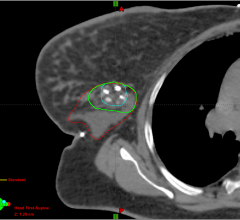

Calypso Medical Technologies, Inc. officially launched its recently FDA 510(k) cleared Calypso 4D Localization System at ASTRO, providing a new technology for real-time target localization and tumor tracking for a variety of clinical applications.

The 4D Localization System utilizes electromagnetic technology in conjunction with Calypso’s implanted Beacon Electromagnetic Transponders, in the prostate, to provide tumor location information during external beam radiation therapy without adding ionizing radiation.